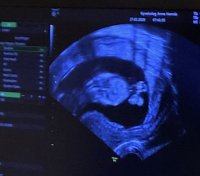

Nub teorien er vel fra tidligst 12 uker. Før det er det stor sjangs for at nub'en "reiser seg", altså at det ser ut som jentevinkel og så blir det guttSlenger meg påSyns det ser ut som jente på meg, men er vel mer troverdig etter uke 12. Var 11+4 her. Spurte om å få filme litt, og da var det lettere å lete etter nubben i sakte film